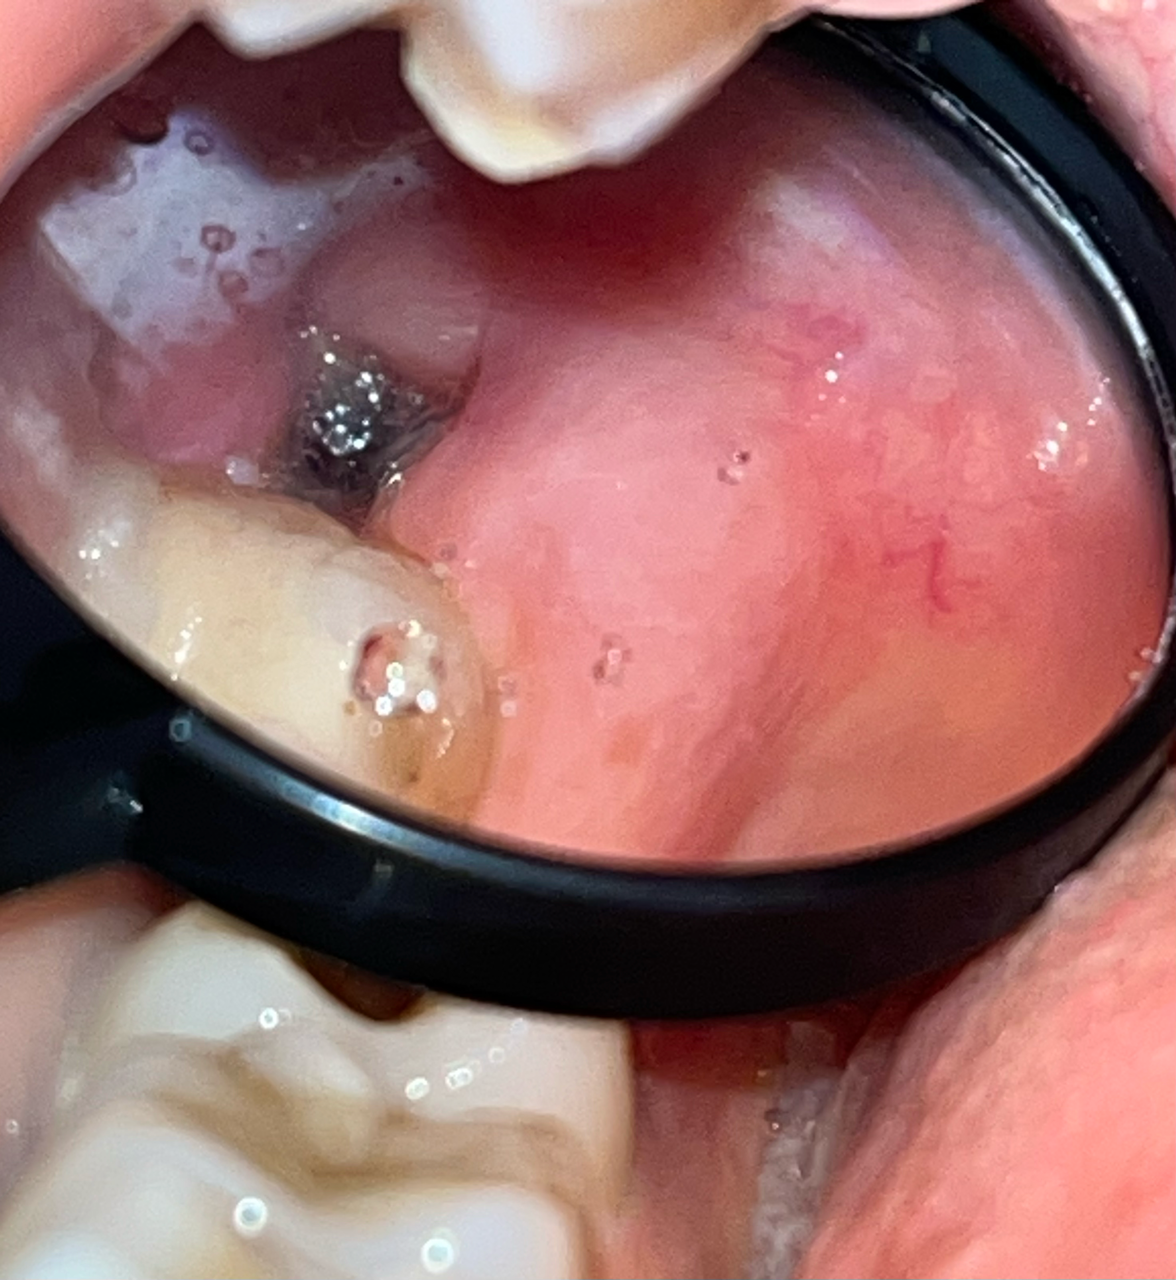

Хронические заболевания: не указаны

Здравствуйте, сегодня третий день после удаления верхнего зуба мудрости, удаление простое, без швов, зуб не ретинированный. Подскажите, пожалуйста, нормально ли проходит заживление и не похоже ли внешне на сухую лунку? К сожалению, лучших фото сделать не удалось. Вчера после чистки зубов было немного кровавой слизи после легкой ванночки хлоргексамедом. Боль слабая, при разговоре и жевании, купируется обезболивающим. Антибиотик не был прописан, контрольного обследования тоже не были назначено. Ем я мягкую пищу и рот не полоскала активно. Спасибо большое заранее за ответ и хорошего дня!

Добрый вечер.

На фото все нормально. Описание вашего состояние тоже соответствует норме. Если вы ожидаете развития альвеолита со стреляющими болям, то можно расслабится, т. к. на 4-ый день этого уже не произойдет.

"нормально ли проходит заживление" - Да, нормально.

"и не похоже ли внешне на сухую лунку? " - Нет, не похоже.